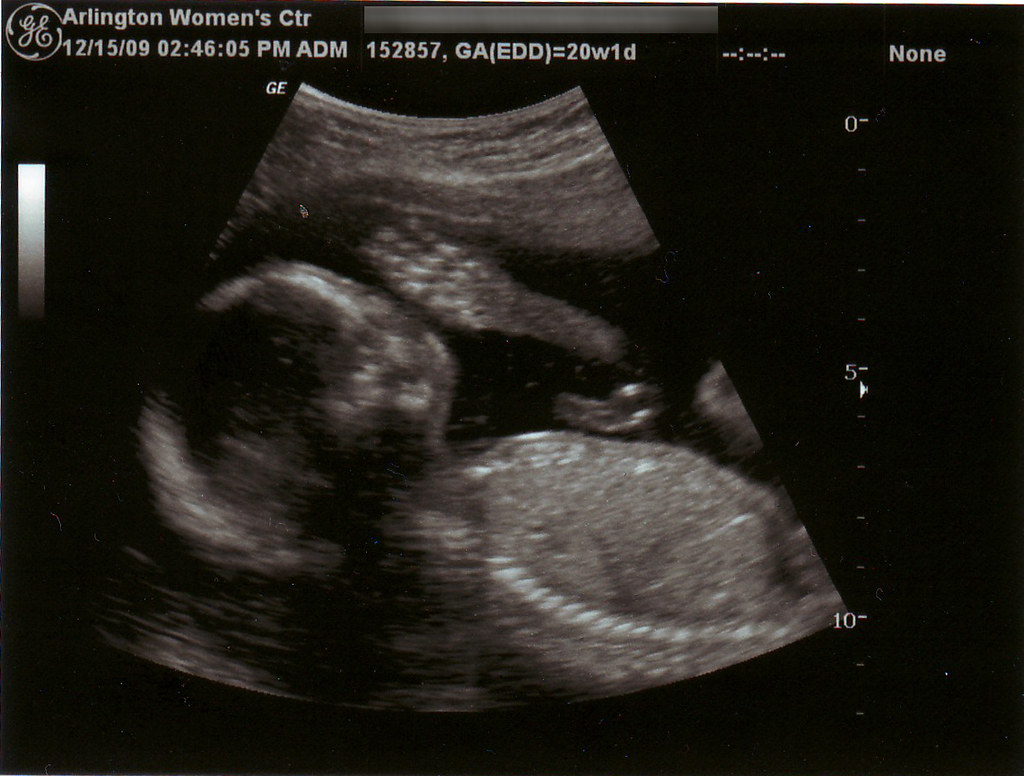

Sul tema Zeta ha intervistato la ginecologa Marina Toschi, membro della rete Pro-choice/RICA: «Su questa fake news le associazioni antiabortiste vogliono basare un referendum popolare, entrando nel rapporto medico-paziente. Da ginecologa non posso essere obbligata da una legge, soprattutto perché gli ultrasuoni utilizzati all’interno della pancia sono dannosi per l’embrione. Dal punto di vista medico non ha rilevanza far sentire il cuore, se non per far soffrire una donna. Inoltre, nelle prime sei settimane non si vede e non si sente nulla. Lo scopo quindi è rendere sempre più difficile l’applicazione della legge 194»

La dottoressa Toschi parla anche di scorretto uso delle parole, per minare la psiche di una paziente: «È scorretto nel linguaggio medico chiamarlo “feto” poiché nelle prime dodici settimane si ha solo un embrione. Il battito del bambino non c’è, perché non c’è bambino. È solo l’inizio di un abbozzo cardiaco che si sente in maniera ritmica. Quindi a livello embriologico non stiamo parlando di un vero organo. Cerchiamo di usare termini corretti, senza distorcere la realtà, perché così facendo si spinge una persona a prendere una decisione piuttosto che un’altra».

Di Martino spiega che l’interruzione volontaria di gravidanza è pratica autorizzata per legge in numerosi paesi nel mondo, soprattutto in Occidente, a discrezione della donna e nei primi mesi della gestazione. Ci sono però paesi che continuano a lasciare la.sola opzione aborto clandestino: «La questione del battito fetale è importante nella legislazione sull’aborto a livello globale. Lo abbiamo visto lo scorso anno in Ungheria, dove è stata approvata una legge che obbliga l’ascolto del cuore del nascituro. Lo abbiamo visto negli Stati Uniti, dopo il ribaltamento della sentenza Roe vs Wade, dove diversi stati americani hanno adottato le cosiddette “Fetal Heartbeat Bill”, che vietano l’aborto nel momento in cui viene percepito il rumore di un cuore, intorno alle sesta settimana. Anche se in quell’età gestazionale quello che si sente è l’attività elettrica di un gruppo di cellule e non un cuore che batte. L’azione che viene portata avanti è la romanticizzazione del feto, i cui i diritti dovrebbero essere posti innanzi a quelli della persona incinta».